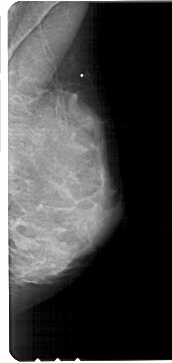

A_1721_1.LEFT_CC

LEFT_CC LINES 4666 PIXELS_PER_LINE 2251 BITS_PER_PIXEL 12 RESOLUTION 43.5 OVERLAY

FILE: A_1721_1.LEFT_CC.OVERLAY

TOTAL_ABNORMALITIES 2

ABNORMALITY 1

LESION_TYPE CALCIFICATION TYPE PLEOMORPHIC DISTRIBUTION CLUSTERED

ASSESSMENT 4

SUBTLETY 3

PATHOLOGY MALIGNANT

TOTAL_OUTLINES 1

BOUNDARY

ABNORMALITY 2